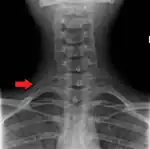

Variations in the number of ribs occur. About 1 in 200–500 people have an additional cervical rib, and there is a female predominance.[13] Intrathoracic supernumerary ribs are extremely rare.[14] The rib remnant of the 7th cervical vertebra on one or both sides is occasionally replaced by a free extra rib called a cervical rib, which can mechanically interfere with the nerves (brachial plexus) going to the arm.

X-ray image of a human chest, with ribs labelled